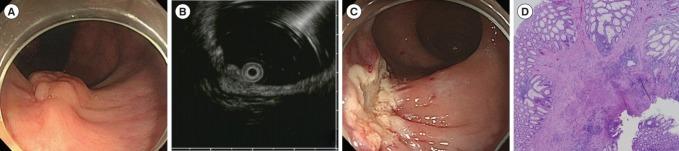

Rectal polypoid lesion with a nodular surface.